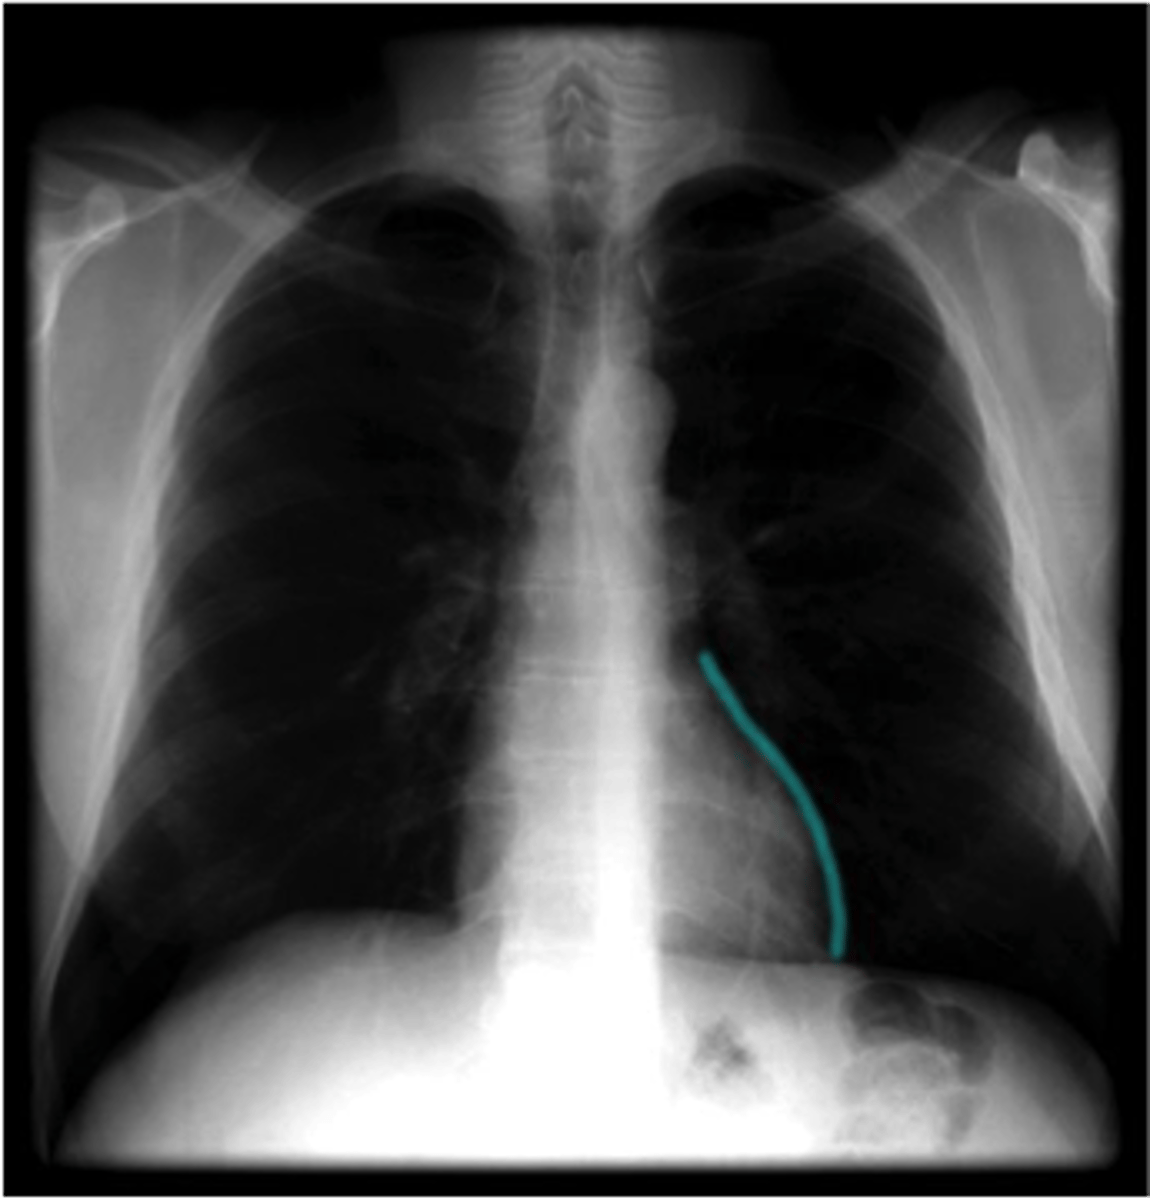

posterior interventricular sulcus